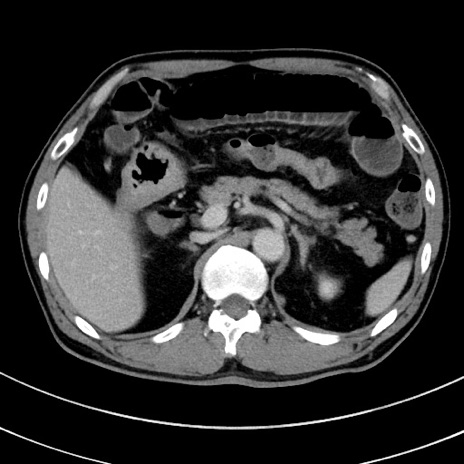

冠状断像

【症例】 60歳代男性

【主訴】 黒色吐物

【現病歴】 4日前から嘔気自覚、2日前の朝食後にも嘔気あり、自分で手で嘔吐反射起こし嘔吐したところ血が混ざっていたため受診。

【既往歴】 5年前汎発性腹膜炎を伴う急性虫垂炎で手術、高血圧、前立腺肥大症、高脂血症

【身体所見】 腹部正中に手術癩痕あり 腹部平坦・軟圧痛なし膨満感あり

【データ】WBC 8400、CRP 4.54